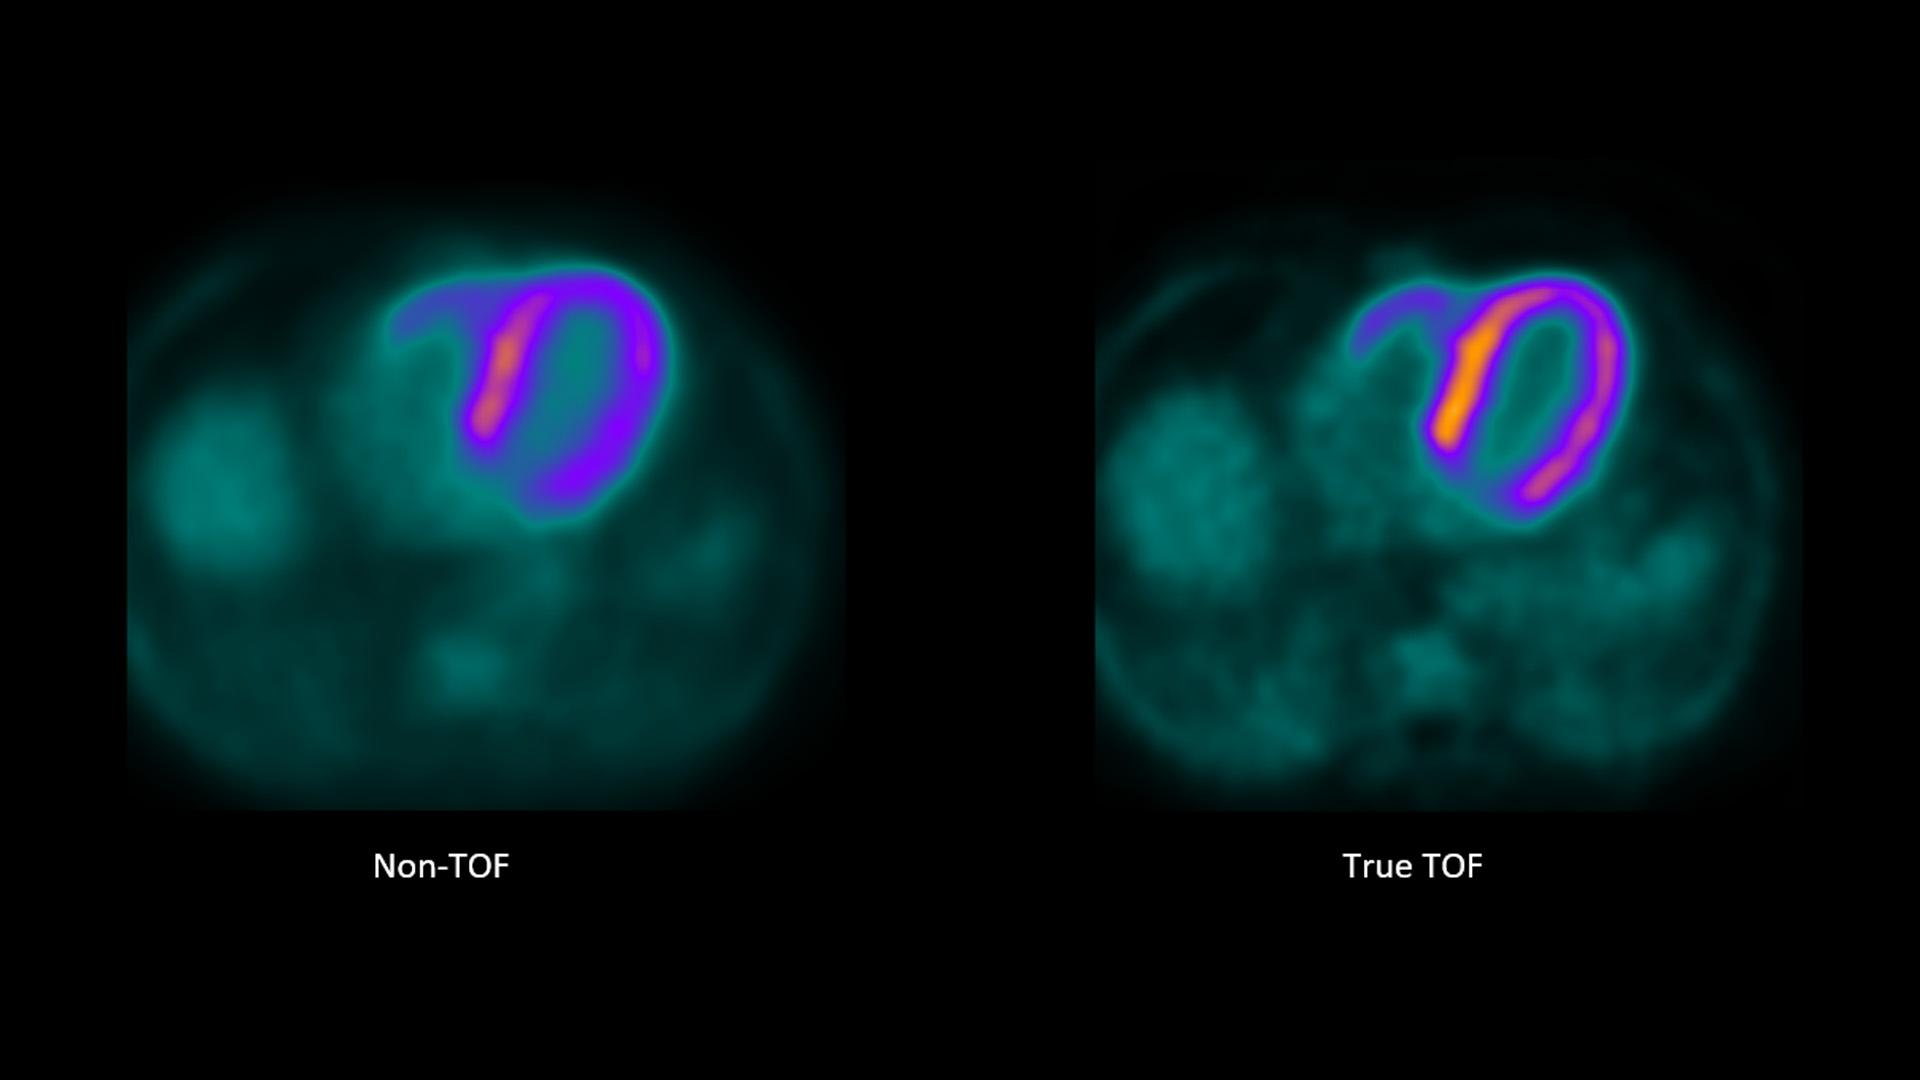

What is the new technology in PET that allows us to get an idea of where an annihilation event happened on the line of response?

Time of flight technology

What is time flight technology?

Where the new technology allows us to better determine where an annihilation event happened based on how soon (time) the photon hit the detector – i.e. it taking 0.5 seconds for the right side vs. 1.5 seconds for the left side → annihilation most likely happened more on the right

How does time flight technology affect how our images on PET turn out?

It decreases our need for having multiple line of responses – able to use shorter line of responses and get rid of all the bad and excess information that makes the images less clear – better able to focus on what we intend to image